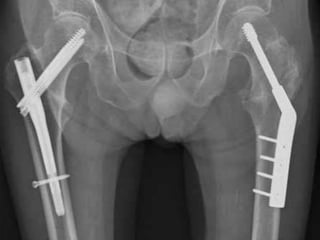

SLIDING HIP COMPRESSION SCREW

Indications

• stable intertrochanteric fractures

Outcomes

• equal outcomes when compared to

intramedullary hip screws for stable

fracture patterns

• The sliding hip screw is the most widely used implant for stabilization

of both stable and unstable intertrochanteric fractures.

• Sliding hip screw side plate angles are available in 5 degree

increments from 130 to 150 degrees.

• The 135 degree plate is most commonly utilized; this angle is easier

to insert in the desired central position of the femoral head and neck

than higher angle devices and creates less of stress

SLIDING HIP COMPRESSIONSCREW Indications • stable intertrochanteric fractures Outcomes • equal outcomes when compared to intramedullary hip screws for stable fracture patterns

• 19.

• The slidinghip screw is the most widely used implant for stabilization of both stable and unstable intertrochanteric fractures. • Sliding hip screw side plate angles are available in 5 degree increments from 130 to 150 degrees. • The 135 degree plate is most commonly utilized; this angle is easier to insert in the desired central position of the femoral head and neck than higher angle devices and creates less of stress